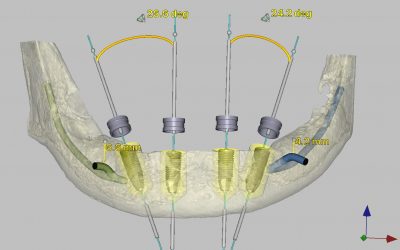

También es preciso hacer constar que otro tipo de intervenciones quirúrgicas en el mismo área pueden presentar como complicación esta anestesia del labio inferior. Este hecho puede ocurrir con más frecuencia cuando la propia lesión engloba al nervio y, en ocasiones, hemos constatado una afectación del mismo por la propia naturaleza de la lesión. Algunos ejemplos de intervenciones que pueden afectar al nervio serían: la extirpación de quistes mandibulares, resecciones de tumores o las reparaciones de las fracturas mandibulares. También hemos observado la anestesia del labio inferior tras la colocación de implantes osteointegrados, muchas veces por mala planificación y ejecución del caso por parte del profesional y otras como una complicación directamente provocada por la propia inflamación periimplantaria, hecho que, por otro lado, es totalmente inevitable e incontrolable por ser inherente a todo tratamiento quirúrgico.